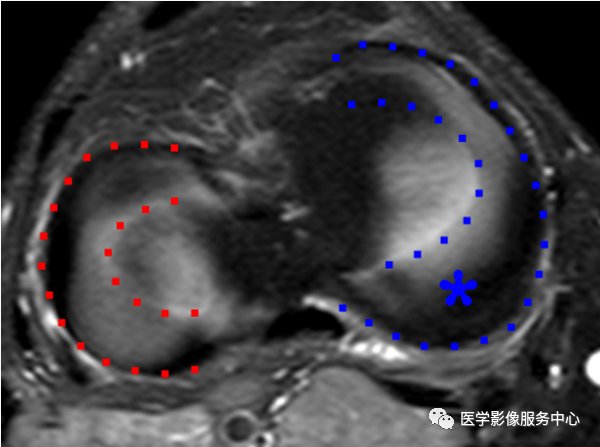

外侧半月板呈“O”(红色轮廓)内侧半月板呈“C”(蓝色轮廓),后角(星号)